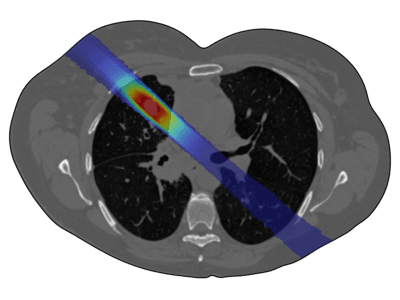

In this study, the COMSOL Application Builder was used to design a user-friendly and accessible GUI for exploring complex radiation dose distributions without requiring simulation expertise. Users, typically at the high school level, can explore core physics principles such as particle–tissue interactions, energy deposition (dose), beam energy and intensity, and the superposition of multiple beams. Users can select from a variety of realistic medical images, specify the size and location of the target region, adjust parameters such as beam energy, particle type, or intensity profiles, and select multiple beam rotation intervals to find an optimal treatment plan that maximizes tumor dose while minimizing exposure to healthy tissue. A built-in optimizer assists in this process.

Anatomical geometries were obtained from thoracic CT scans available in the publicly accessible LIDC-IDRI database. Using ITK-SNAP, the lungs and surrounding tissue were segmented and converted into COMSOL geometries via the Image-to-Curve add-in, which allows assigning different attenuation properties. The 2D FEM model is implemented in COMSOL Multiphysics® and the Particle Tracing Module. Proton beam depth-dose curves are modeled with a simplified Bragg peak description following Krämer & Scholz (2000), while photon attenuation obeys the Beer-Lambert law.